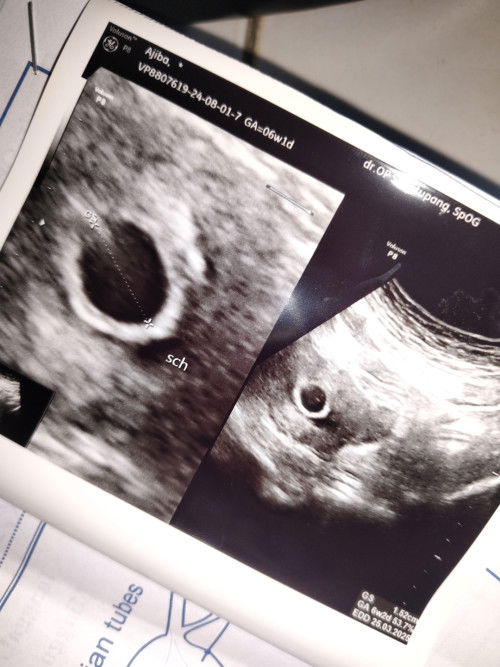

Normal gak sih bun usia kehamilan 6w tapi belum kelihatan janinnya, cuma kelihatan kantung nya aja.

Normal bun aku kemarin gtu 6 week bru kantung aja pas usg lgi 7 week udh ada janinnya bun rajin aja konsumsi asam folat sma mkn telur rebus dan alpukat bun

aman bun, aku beberapa waktu lalu usg 5 week kantong, pas udah 7 week udah ada djj bun, nnti bunda kalau USG lagi pasti insyaAllah udah ada djj sih

coba nanti USG kembali Bun 2 Minggu lagi. saya juga wkt 5 week hanya kantong keliatan. Alhamdulillah 8 week udh ada adek bayinya

sama bun kayak aku kemarin, trus kembali 2minggu lg sekarang udah ada janin & detak jantungnya

sama kayak aku bun. minggu kemarin USG transvaginal masih kelihatan kantong kehamilan aja.

Saya jg bun, 6w3d tp masih kantong aja